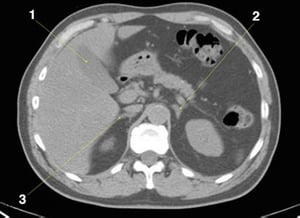

CT-Scan von Abdomen und Becken mit normaler Anatomie ohne Kontrastmittel (Folie 8)

1 = Gallenblase; 2 = linke Nebenniere; 3 = rechte Nebenniere.

© Springer Science+Business Media